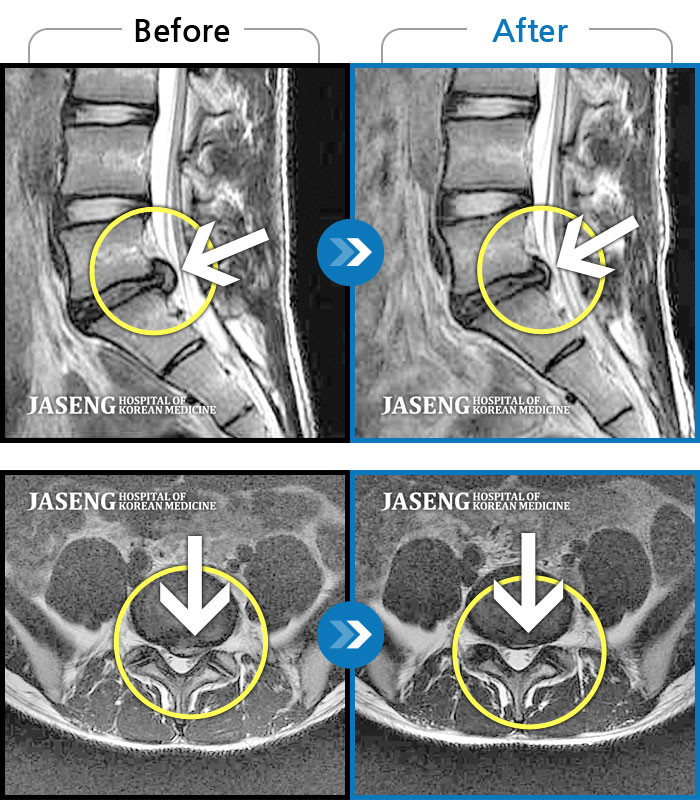

허리디스크

수원 · 김태성 원장

허리 통증과 우측 고관절~하지방사통이 심하여 활동하기 힘든 상태

촬영시기

2021.03.04 ~ 2021.10.06

2022.03.25

조회수 235